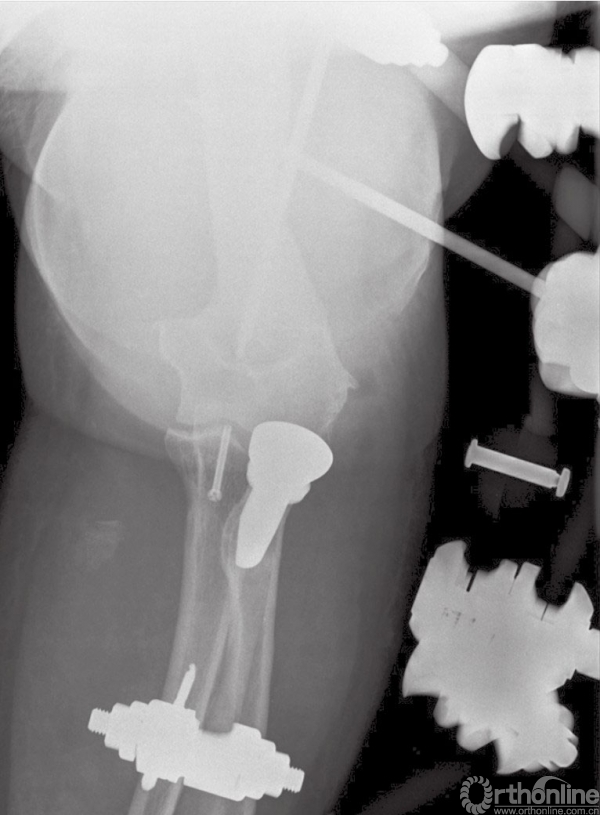

5. 如果发现肘关节稳定性不可靠或者存在再次脱位风险,建议使用铰链式外固定支架。

在内固定完成和韧带的损伤修复后,在手术台上验证患者肘关节的稳定性。如果发现肘关节稳定性不可靠或者存在再次脱位风险,建议使用铰链式外固定支架,这样可以使肘关节获得同轴心的稳定性,并可以使患者在术后早期活动。

对于没有合并并发症的患者,我们也倾向于术后使用铰链式外固定支架,以避免不可控的关节活动。使用外固定支架可以中和修复后骨折端及韧带复合体所受的应力,防止术后早期活动时发生再脱位及内固定失败。外固定支架一般使用6周(图12)。

图12 术后使用铰链式外固定支架,有利于术后软组织损伤恢复及早期活动